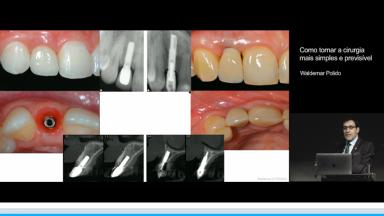

Como tornar a cirurgia mais simples e previsível

Waldemar Daudt Polido

A apresentação demonstra fatores de risco relacionado ao resultado protético com implantes. Ressalta as expectativas dos pacientes no tratamento e como planejar procedimentos cirúrgicos de forma a se aproximar destas expectativas. Para isso, são destacados a importância do conhecimento da anatomia do rebordo alveolar, e como seus defeitos de tecidos duros e moles impactam a morfologia dos tecidos perimplantares. Também, são discutidos estratégias para obtenção de estabilidade através de técnica cirúrgica, conhecimento da macrogeometria e tecnologia de superfície. Além disso, a relevância da  posição ideal para estabilidade tecidual, e como o planejamento virtual e guias cirúrgicas podem auxiliar na obtenção da posição 3D são esclarecidas. Por fim, são descritos também o papel do volume de tecidos duros e as possíveis complicacões relacionadas a erros de planejamento.